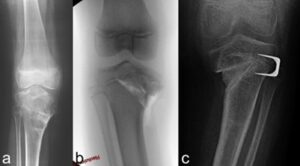

- Tibial plateau elevation osteotomy. This is essential in cases where the varum knee is associated with deformities of the articular surface, to restore its profile. It is usually performed using bone wedges that are added under the growth plate to re-elevate the articular surface.

- Double tibial osteotomy. A unique procedure that includes the two previous osteotomies, so as to simultaneously treat both the varus deviation and the joint deformity.